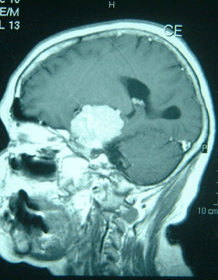

- 脳内出血

脳腫瘍